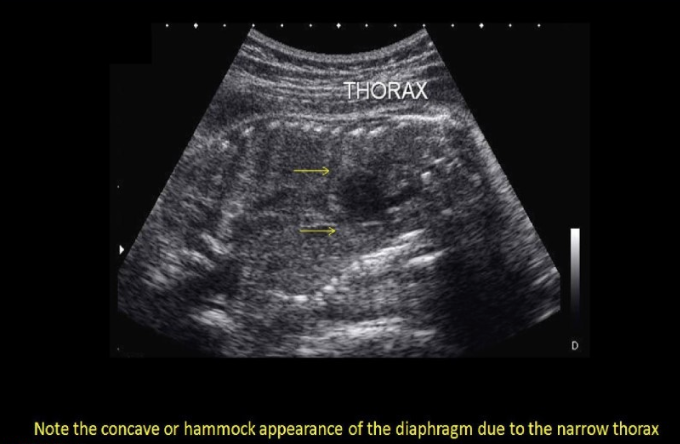

if the radiologist suspects potter syndrome + requests that you perform a thoracic circumference. how will this measurement assist in the dx? Potter syndrome usually shows

.

a) cardiomegaly + diaphragmatic hernia, which will increase the size of thoracic cavity

b) pulmonary hyperplasia, which leads to enlarged thorax

c) a narrow thorax due to acardia

d) a bell-shaped thorax that is much more narrow than the abd cavity